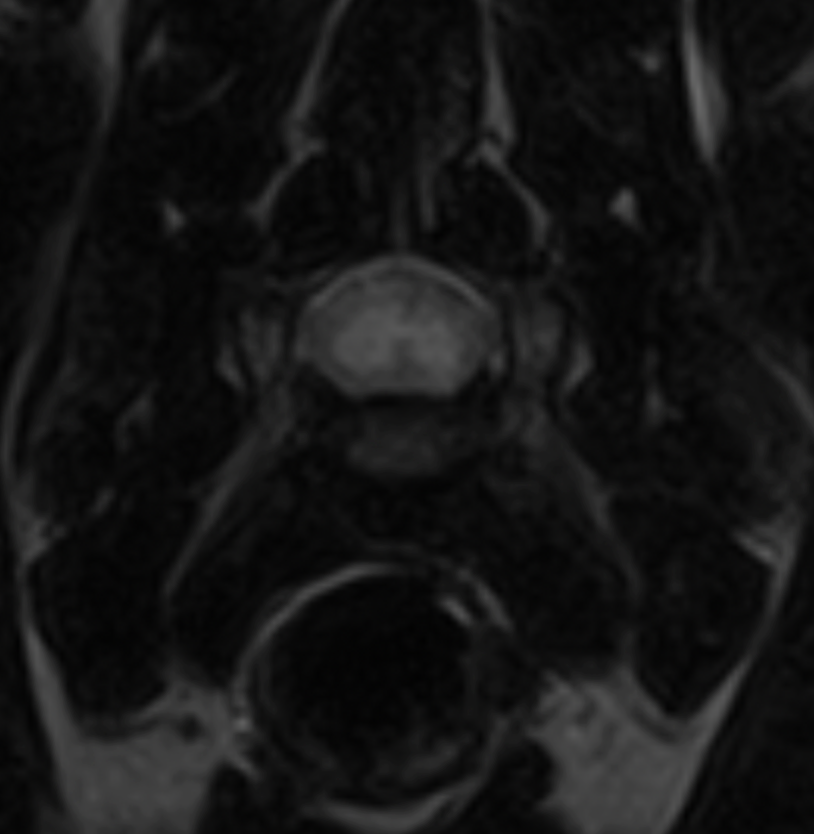

In early 2022, Veterinary Emergency + Referral Centre (VERC) became home to Hawaii’s first Hallmarq 1.5T small animal MRI. It was a milestone for veterinary imaging in the islands! However, before that, many pets with possible brain, spinal cord, or soft tissue injuries were limited to CT scans. And, although fast, CT is not always able to catch the subtle but critical lesions that MRI can detect. The absence of high‑field MRI was proving to be a barrier to diagnosis and effective treatment.

Hallmarq’s small animal 1.5T MRI system is unique in that it is purpose‑built for pets and their anatomy. It is not a repurposed human MRI machine which is often the case. Instead, it delivers superb, detailed images that are needed for a definitive diagnosis in veterinary practice. Features like the V‑shaped patient bed, veterinary‑specific coils, and advanced channels deliver superior imaging of the brain, spinal cord, and delicate structures in animals of all sizes.

Both Hallmarq’s MRI and Remote Operations provide the tools needed by Dr Williamson to support her specialist knowledge. At VERC, advanced imaging is paired with expert interpretation. As a result, neurological conditions once difficult to detect are now diagnosed earlier, treated more effectively, and managed with greater confidence. In the case of beloved cat Oliver, MRI made all the difference to his diagnosis: